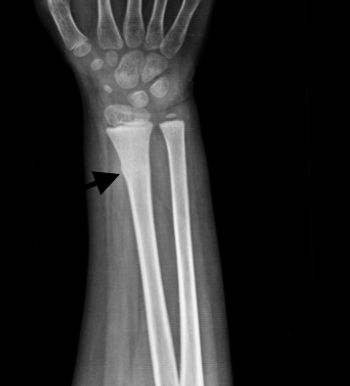

A 7-year-old male presented with pain after falling on an outstretched hand.